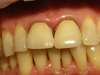

Cas n°1 :

Cas N°2

cas n°3 :